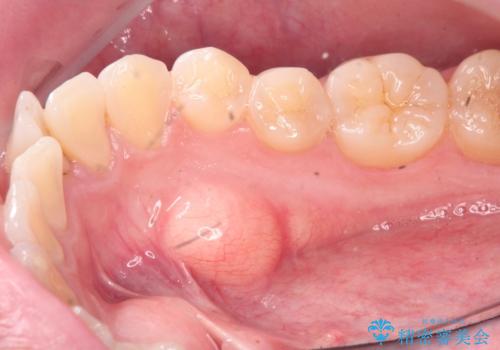

[ 舌小帯の形成術 ] ラ行の発音を改善したい

- 「ラ行の発音がしづらい、改善したい。」、と舌小帯の形成の相談に来られました。

形成術を行うことで、滑舌の改善が見込めることから即日で舌小帯の形成術を行うこととしました。

術後、「かなり発音がしやすくなりました。」

と治療結果に喜んでいただくことができました。